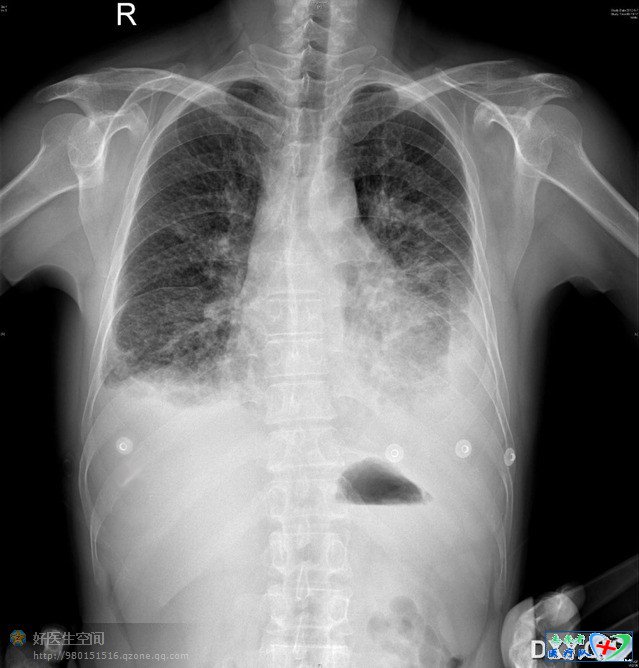

由于这个帖子我写写停停,因此大家如果看到这个彩蛋才是真正的完结篇,上面说过了,个人感觉这个定位有点偏下,按我们经典的理论在肩胛下线上肺下界在第10肋间隙,也就是说我们要尽量避免在这个位置或这个位置以下进针以免穿到腹腔脏器,这个位置我个人感觉偏低,当时轮转医生带病人下去,现在我用什么办法印证我的想法,刚好病人今天要复查抽液后情况,我在标记的地方贴上心电监护的贴片,上面有金属纽扣,我在同一水平线贴了几个,就这么简单,

彩蛋就在下图,亲们不要浪费这个机会,这个定位点在8肋间?9肋间?10肋间?11肋间?你们的答案是什么?

呵呵,我猜错了,虽然体表上感觉偏低,但确实是很标准的肩胛下线第9肋间隙,感谢B超医生的精彩定位,感谢亲们的支持,感谢好医生 ,非常感谢!(完结)